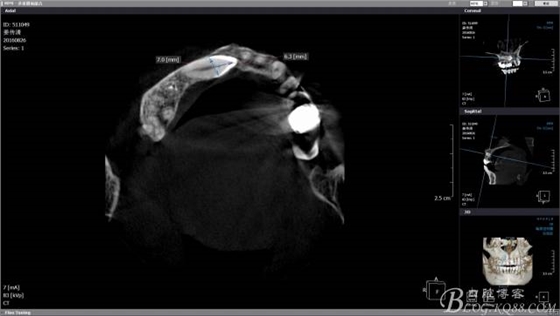

CBCT檢查:A1和A4根尖區(qū)有一水平橫置多生牙,多生牙會(huì)影響A1到A4區(qū)域的種植手術(shù),建議外科手術(shù)拔除多生牙。

CBCT檢查尖牙牙冠靠近鼻腭神經(jīng),牙冠靠腭側(cè)且骨皮質(zhì)較薄,牙根靠唇側(cè),雖然走唇側(cè)拔除阻生牙有一個(gè)很好的視野,但是考慮到微創(chuàng)的理念和加上之后會(huì)開展種植手術(shù),所以堅(jiān)決不走唇側(cè)去破壞骨皮質(zhì)。

CBCT上模擬T形分壓,測(cè)量長度,分離牙冠的時(shí)候長柄裂鉆就是我們手中的尺子,分冠時(shí)候一定切忌老老實(shí)實(shí)按照?qǐng)D中的7mm去分冠,很容易穿透唇側(cè)骨板,一定要向做上頜竇提升一樣差個(gè)1mm為最合適。